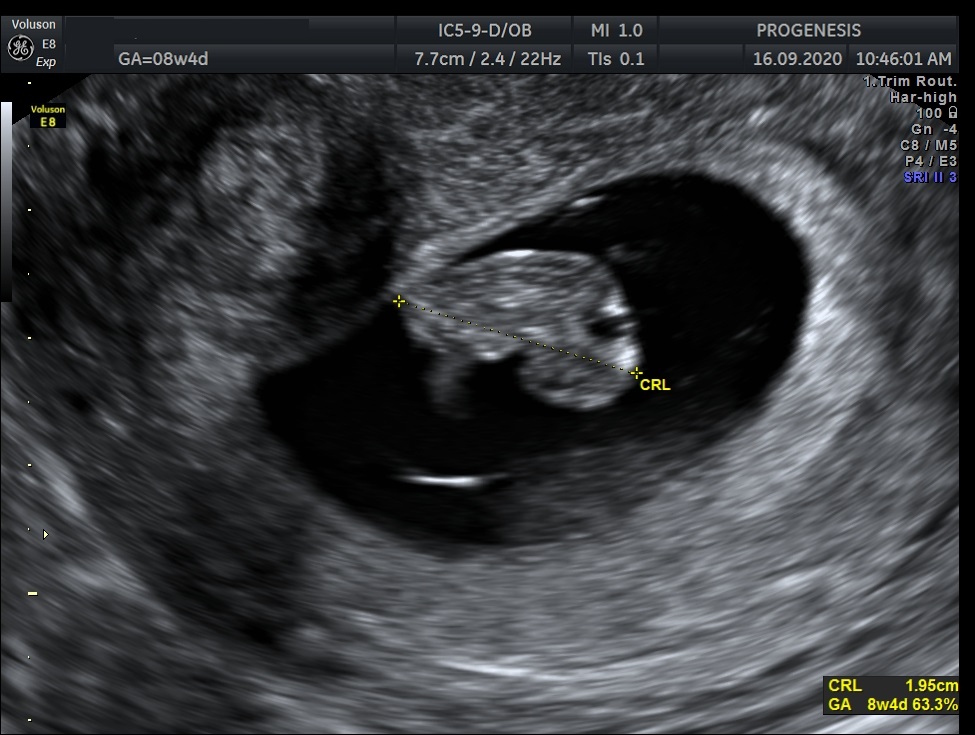

Υπερηχογράφημα Αρχόμενης Κύησης

(6-11 εβδομάδων)

Σκοπός της εξέτασης είναι να επιβεβαιώσουμε ότι υπάρχει φυσιολογικά εξελισσόμενη κύηση μέσα στη μήτρα, αναγνωρίζοντας έμβρυο με καρδιακή λειτουργία, και  αποκλείοντας την εξωμήτριο  κύηση.

Επιπλέον, αναγνωρίζεται ο αριθμός των εμβρύων, έχουμε μία πρώτη εκτίμηση της ηλικίας κύησης καθώς και της χοριονικότητας (εάν δηλαδή τα έμβρυα μοιράζονται τον ίδιο πλακούντα) στη περίπτωση της πολύδυμης κύησης.